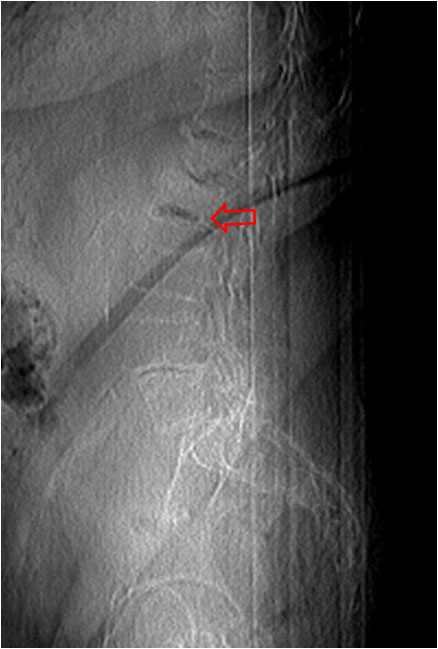

SIGNO DE LA DOBLE LÍNEA

Signo de osteonecrosis avascular visible en la resonancia magnética, en imágenes potenciadas en T2. En la osteonecrosis avascular se ve una línea de alta intensidad de señal rodeada por un anillo paralelo de hiposeñal, con frecuencia de bordes serpiginosos. La línea hiperintensa (flecha negra) corresponde a tejido de granulación hiperémico y la línea externa hipointensa (flecha roja) corresponde a hueso escleroso.